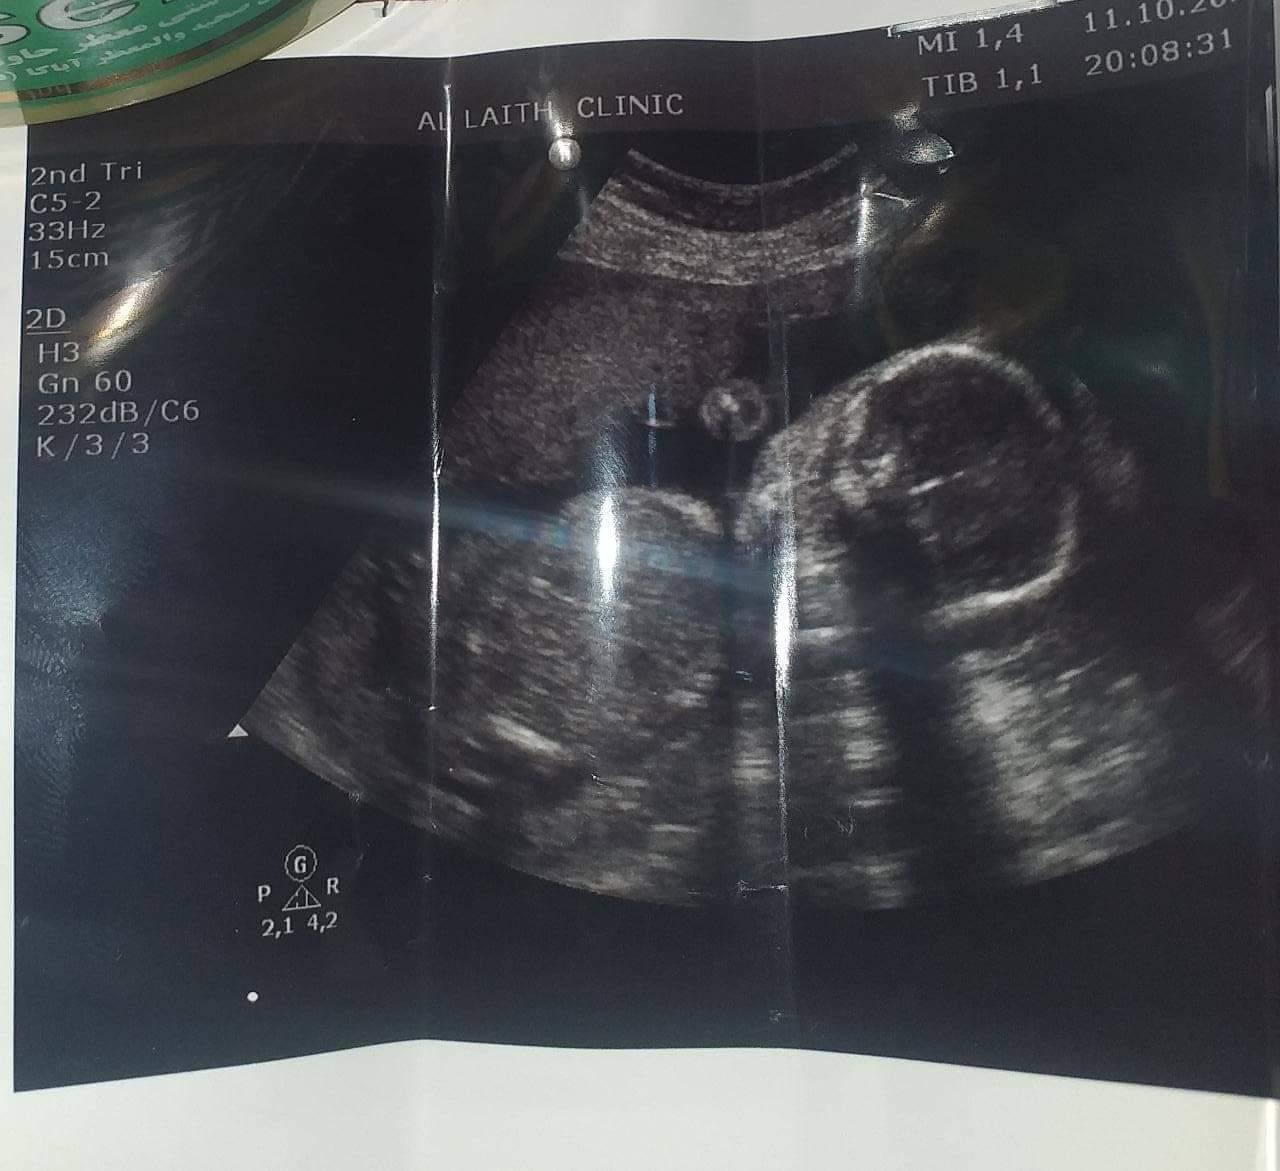

وبفضل الله قد انهيتُ هذا المعاناة وكنت سبب في تحقيق حلم تكوين العائلة وإعلان شبه نهائي نهاية العقم أو تأخير الحمل عند النساء حيث بلغ العدد الإجمالي للنساء اللواتي أصحبنا حوامل أكثر من ١٠٠ امرأة أوعزت العضب السبب لتزايد عدد عمليات الناظور البطني والرحمي بشكل منقطع النظير لم يشهده العراق وتحديداً في محافظة ذي قار إذ تعد رابع محافظة من حيث التعداد السكاني. وكما بينّت الدكتورة الإستشارية أزهار العضب أنها قد تم تكريمها بعدة شهادات شكر وتقدير ودرع التميز من وزيرة الصحة العراقية السابقة وبهذا تعد الطبيبة الأولى والوحيدة المخولة رسمياً بإجراء عمليات الناظور البطني في المحافظة وأيضًا كونها أول طبيبة من أهالي ذي قار تحصل على لقب طبيب استشاري في أمراض النساء والتوليد وأن هذا يعتبر إنجازًا للمرأة العراقيه بزمن كورونا ..